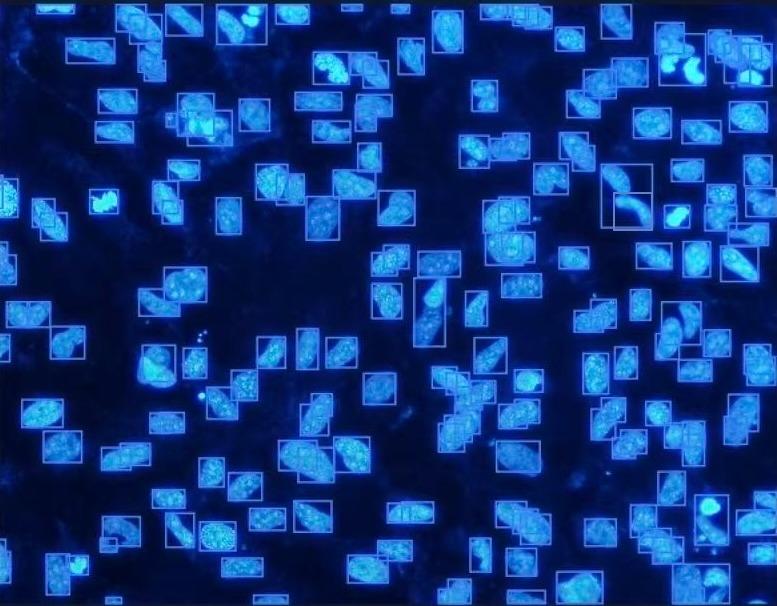

AI-driven cell detection, segmentation and quantification

AI-powered detection, segmentation, and counting with scientific precision.

Support for large, multi-gigapixel images. Consistent, reproducible analysis across experiments. Expert-in-the-loop correction and validation.